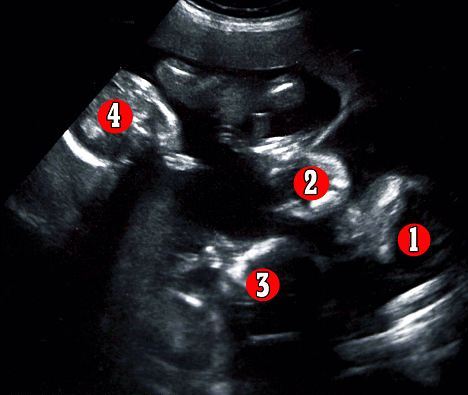

«Έκανα τον πρώτο υπέρηχο στις 17 εβδομάδες. Μέχρι τότε η εγκυμοσύνη μου ήταν ακριβώς όπως και στο πρώτο μου παιδί. Όταν πήγα στο νοσοκομείο η μαία μου είπε ότι δεν είχα μόνο ένα έμβρυο στην κοιλιά μου. Μετά τη ρώτησα αν βλέπει δύο μωρά και μου απάντησε: “Όχι, είναι τέσσερα!”» διηγείται η ίδια.

«Δε μπορούσα να το πιστέψω. Κοιτούσα την οθόνη σοκαρισμένη. Δε μπορούσα να το χωνέψω, ταράχτηκα και της ζήτησα να κλείσει την οθόνη γιατί δεν ήθελα να την κοιτάω. Με πήραν οι γονείς μου τηλέφωνο, αλλά δεν μπορούσα να τους μιλήσω γιατί έκλαιγα με αναφιλητά».